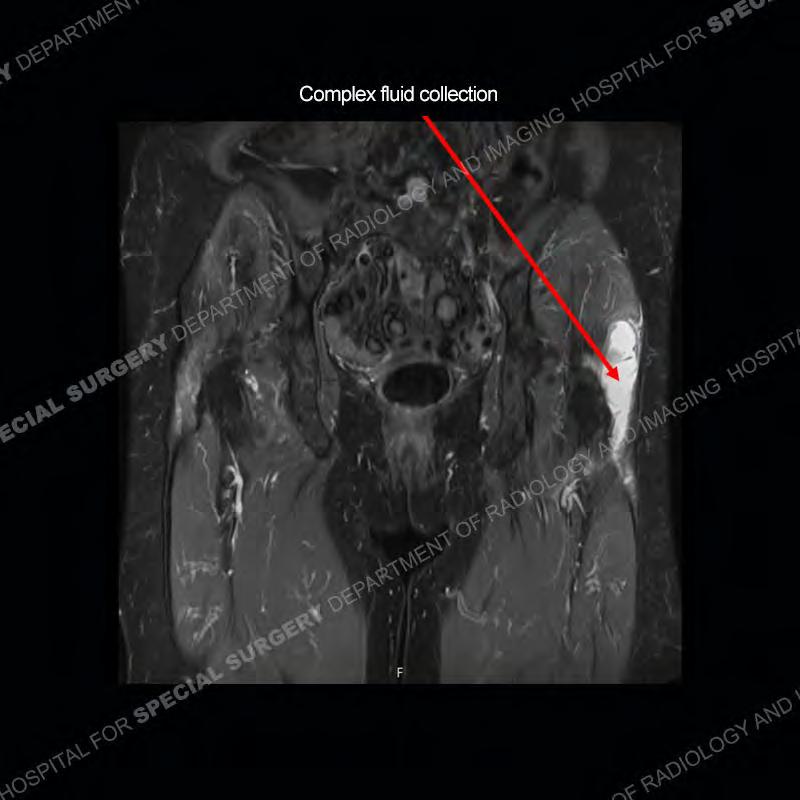

The radiograph is not particularly contributory in this case. The MRI demonstrates markedly abnormal architecture of the gluteus minimus and anterolateral band of the gluteus medius. Portions of the tendons are high signal, portions are highly attenuated, and portions are disrupted. A large, complex fluid collection is present in the adjacent soft tissue.

Not as much of a diagnostic dilemma as many of the other cases shown but just a nice example of the pathology seen of the gluteal tendons and a cause of trochanteric pain. Although, frequently thought of in isolation, trochanteric bursitis or bursal thickening is much more commonly a reactive change to underlying pathology of the subjacent gluteal tendons. The gluteus medius is divided into a posterior band and an anterolateral band. Tendinosis and partial tearing very commonly will involve the gluteus minimus and especially the more posterior fibers and then propagate into the anterior lateral band of the gluteus medius. Involvement of the posterior band of the medius is much less common and engenders a marked degree of functional impairment.

The bursae about the greater trochanter can be a little bit confusing especially given the terminology. Trochanteric bursitis is implied to mean the subgluteus maximus bursa which is present deep to the maximus and just lateral/superficial to the trochanter. That is the bursa involved in this case. In this case the complexity of the bursa relates to the tendon tearing with inflammatory change and probably hemorrhage accounting for the complexity. Two other, less frequently involved bursa are also present. The subgluteus medius and subgluteus minimus bursa are found just deep to the named tendons. Although pathology does frequently follow the previously described pattern it is possible to have isolated pathology to either the medius or minimus.